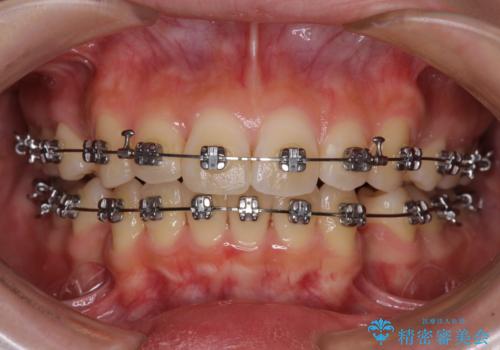

- メタルブラケット

- 治療期間

- 1年5ヶ月

上下左右4本抜歯する場合には、通常2年から2年半ほどの期間を要しますが、僅か1年半で終了することができました。